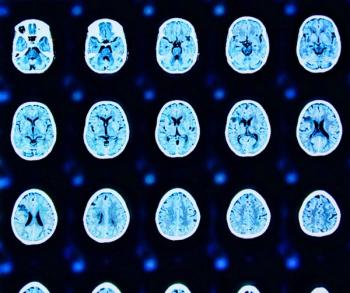

For children who had a head CT scan, there was a 35 percent increased relative risk of developing hematologic cancer, according to a new study examining data from over 3.7 million children with a mean follow-up period of 10.1 years.